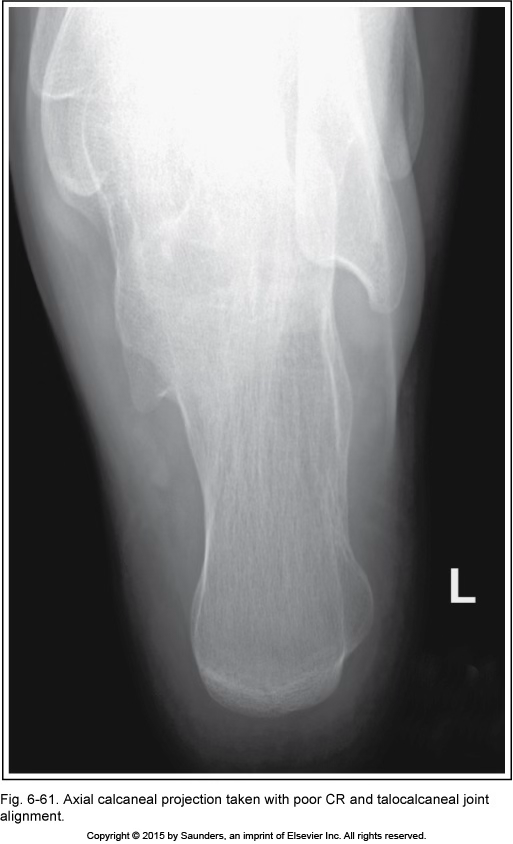

Axial calcaneus

accurate positioning

poor CR and talocalcaneal jt alignment

cant see jt space